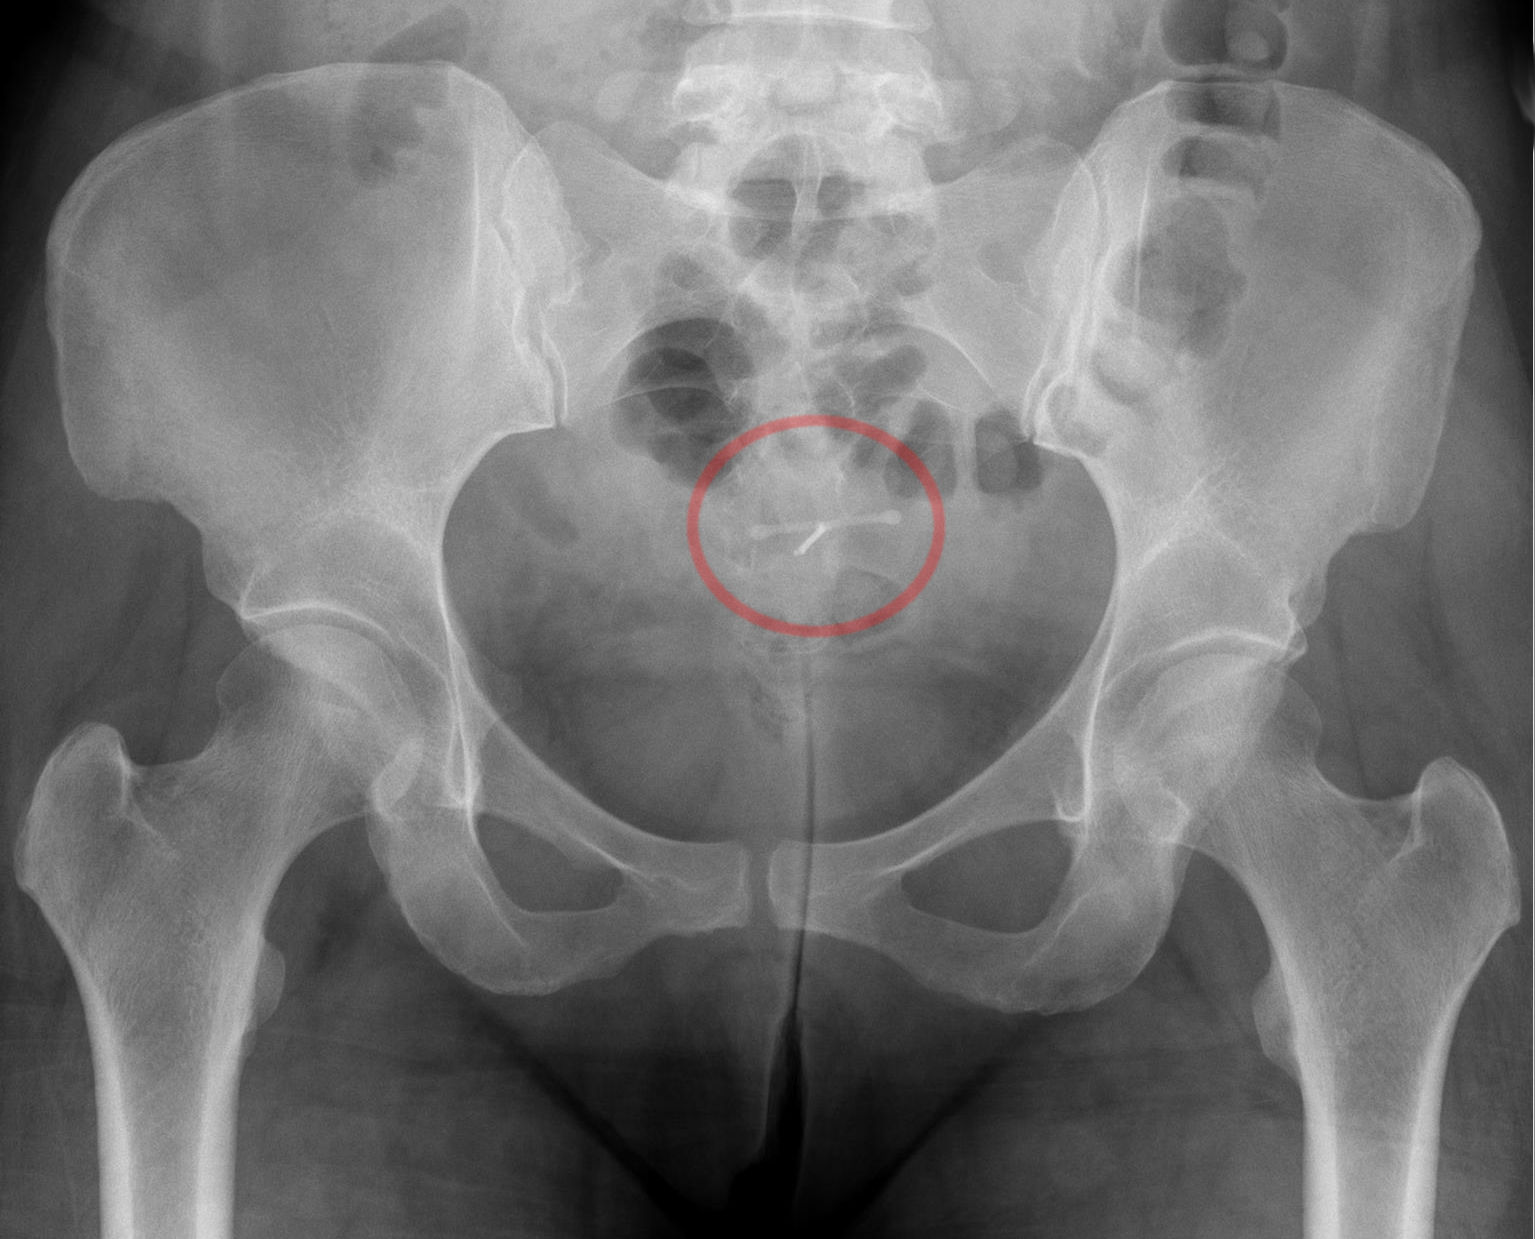

drug nameLiletta

classificationIntrauterine device (IUD) releasing levonorgestrel

indicationsContraception in appropriately selected individuals. Generally used for long-term, reversible contraception for women of reproductive age.